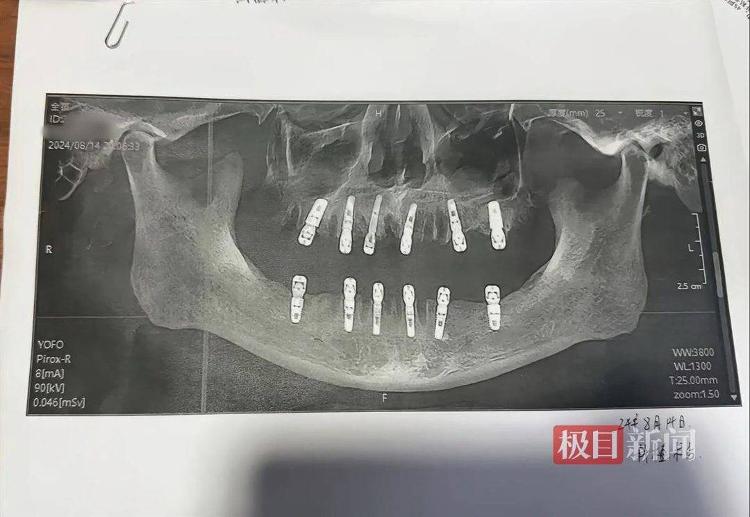

相关口腔影像资料(图源当事人社交账号)

连日来,该网友发帖称,其父亲在金华永康市一家医院拔牙后去世。9月2日晚,该网友发布的一张声明显示,其家属于8月14日在永康市某口腔医院进行23颗牙齿拔除、12颗牙齿种植后一直疼痛不止,后来心脏骤停死亡,目前已经委托律师事务所依法维权诉讼。3日,极目新闻记者私信了这名网友,暂未得到回复。

武汉市第四医院口腔医学中心主任向国林告诉极目新闻记者,在患者出现牙齿松动、残根残冠无法保留、需要拔除做全口种植修复的情况下,可以采取即拔即种的牙齿修复方式。正常成人共有28至32颗牙齿,目前没有针对拔牙数目的具体规定,一般来说,一次性拔除的牙齿最多在十多颗,23颗数目较多,既需要诊所及医生具备一定的资质和水平,也需要考虑患者的身体承受能力。